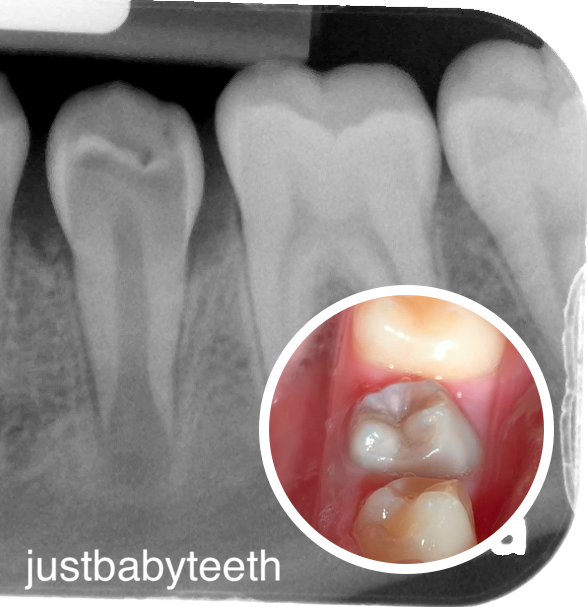

Mandibular distraction osteogenesis effects

Permanent molar malformation and destruction as a result of mandibular distraction osteogenesis surgery π¦·π